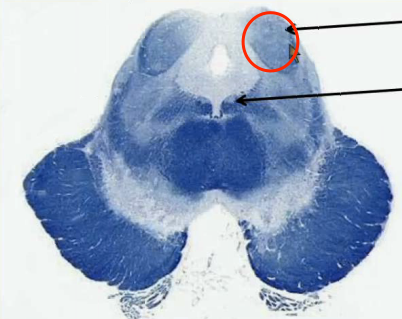

Where in the upper pons is the structure involved in focusing attention on stimuli and initiating sleep located?

Locus ceruleus in the dorsal part of the upper pons.

Where is the structure located in the brainstem that receives 2 point tactile discrimination and vibration sensation for the face?

Principal sensory nucleus in the dorsal middle pons.

Where is the structure located in the brainstem that innervates the muscles of mastication?

Motor nucleus of V in the dorsal middle pons.

Where is the structure located in the brainstem that innervates the lateral rectus muscle?

Abducens nucleus located in the dorsal lower pons, just anterior to the 4th ventricle. Note that its nerve goes through the tegmentum and basilar pons (inferior pontine sulcus) as it exits the brainstem.

Where is the structure located in the brainstem that innervates muscles of facial expression?

Facial nucleus, in the middle lower pons. Note that it slingshots its axons around the abducens nucleus before exiting the anterior lower pons.

Where is the structure located in the pons that receives pain, light tough and temperature signals from the face?

Spinal Vth nucleus and tract in the lower pons.